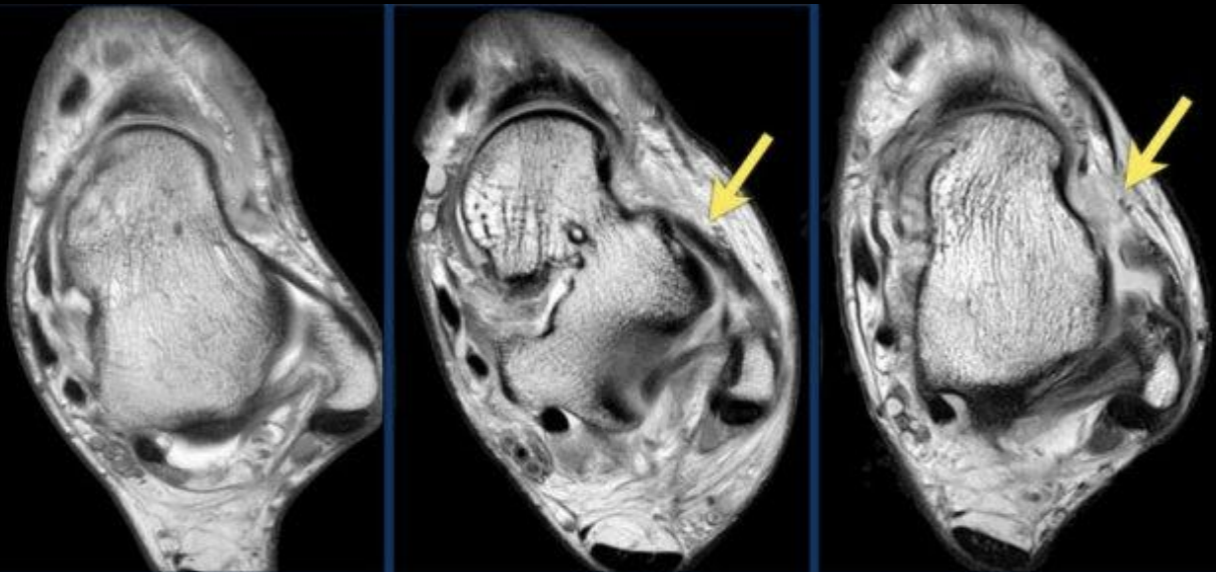

A

Lesión ATFL

I, II y III

Grados Esguince